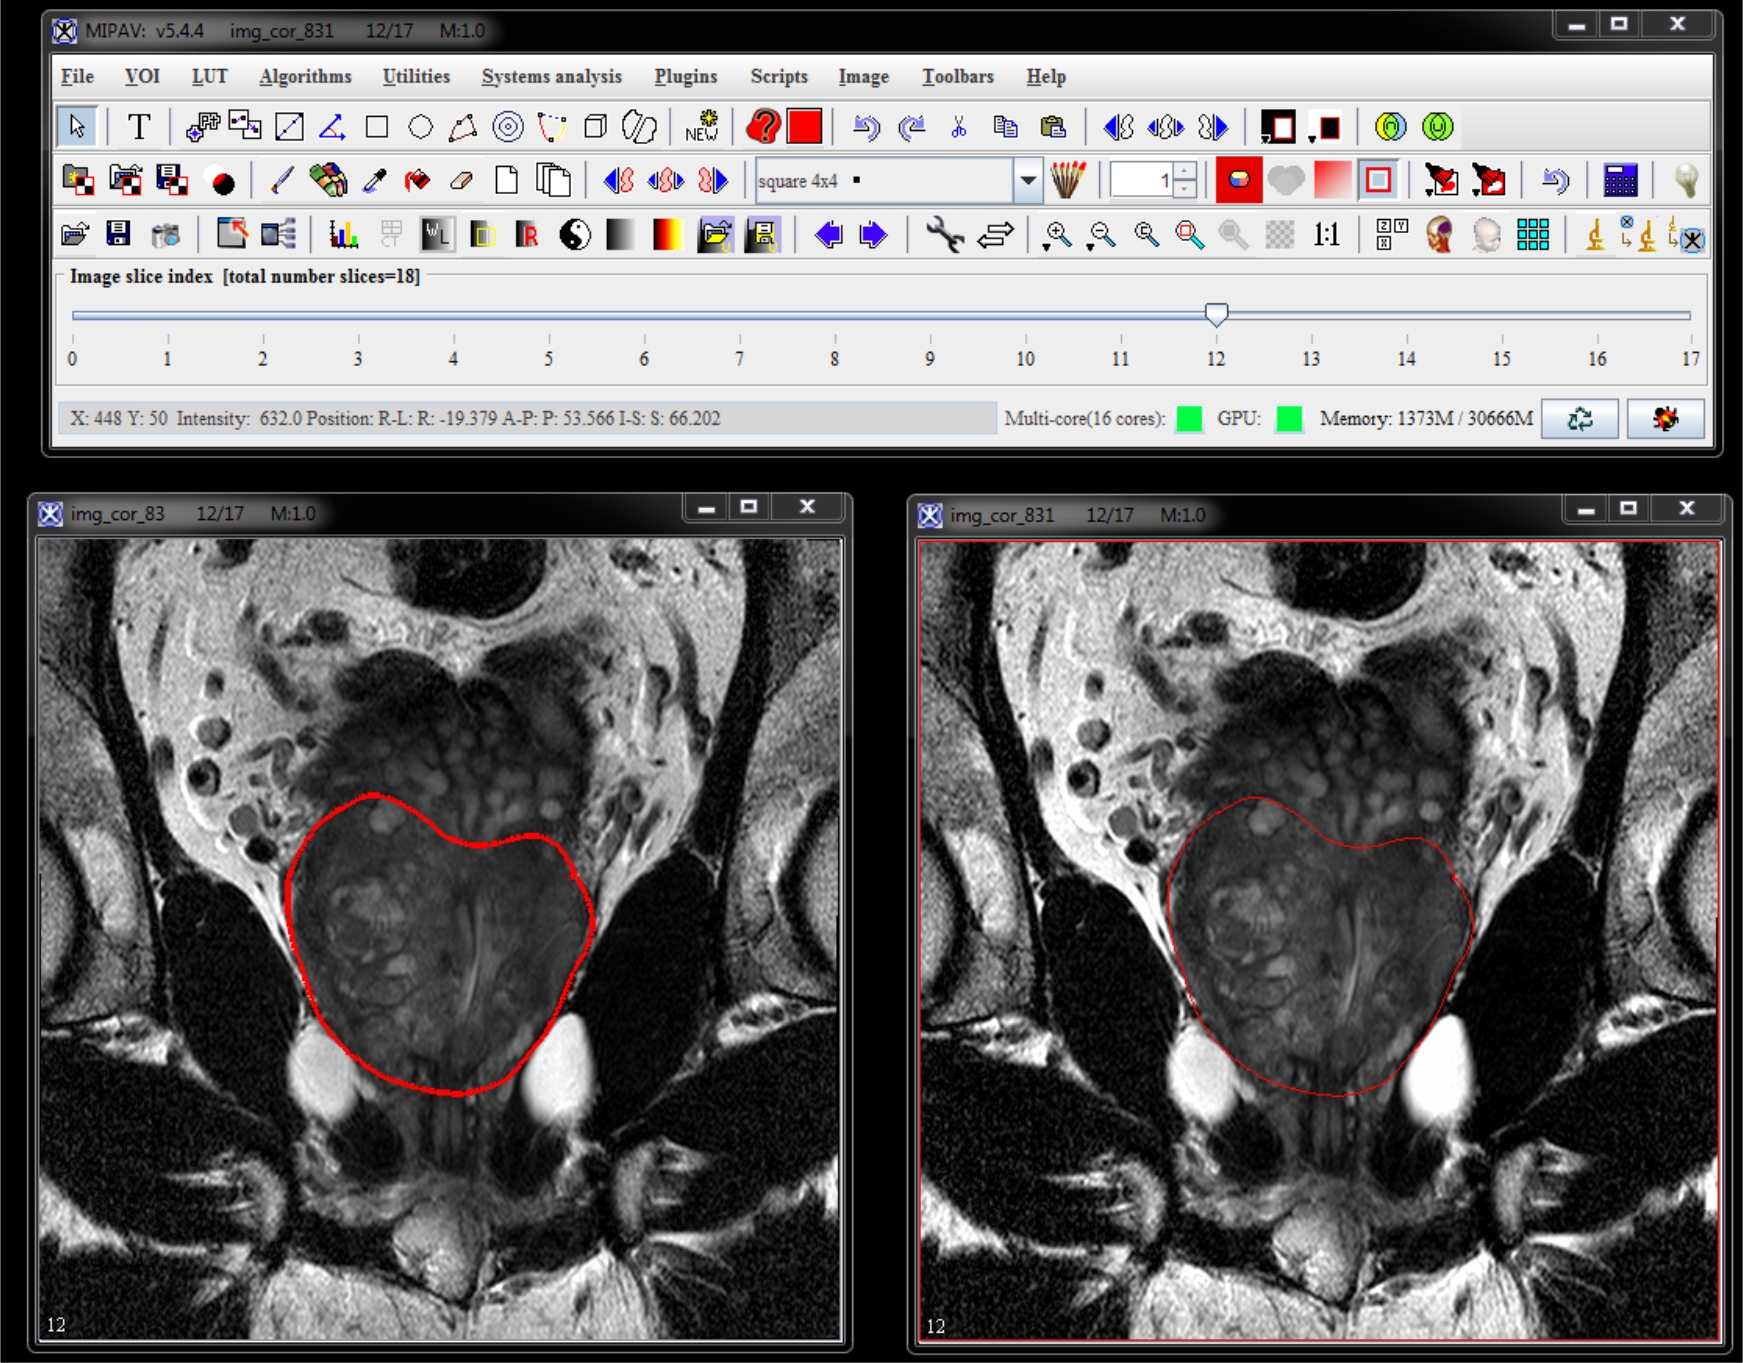

Sagittal and coronal images. Repeat the same process of delineating and smoothing VOIs for both sagittal and coronal images. In the sample image dataset provided, the saggital image name is img_sag_83 and the coronal image name is img_cor_83. See Naming Conventions.

| coronal | img_cor_83.xml | voi_cor_83.xml |

We use the semi-automatic segmentation dialog to segment the MRI prostate image. Before proceeding, please, make sure you open 3 orthogonal prostate images with VOIs - img_ax_83.xml and voi_ax_83.xml, img_sag_83.xml and voi_ax_sag.xml, and img_cor_83.xml and voi_cor_83.xml.

For each named VOIs based mask, the console window shows the number of voxels and volume. Created VOIs are used for the surface reconstruction step. Each VOI contour has 100 points.

Axial image VOIs: number of voxels = 333795 volume = 74871.586 mm^3 Sagittal image VOIs: number of voxels = 340633 volume = 76405.41 mm^3 Coronal image VOIs: number of voxels = 320149 volume = 71810.766 mm^3 time elapse = 1 mins 55 sec